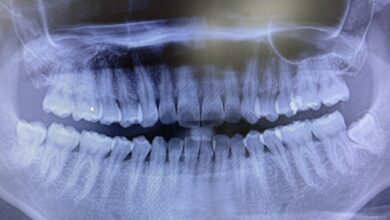

セラミック矯正とは、歯列矯正の一種で、目立ちにくいセラミック製のブラケット(矯正装置)を使用して歯列を矯正する方法です。今回は、セラミック矯正について詳しく説明していきます。